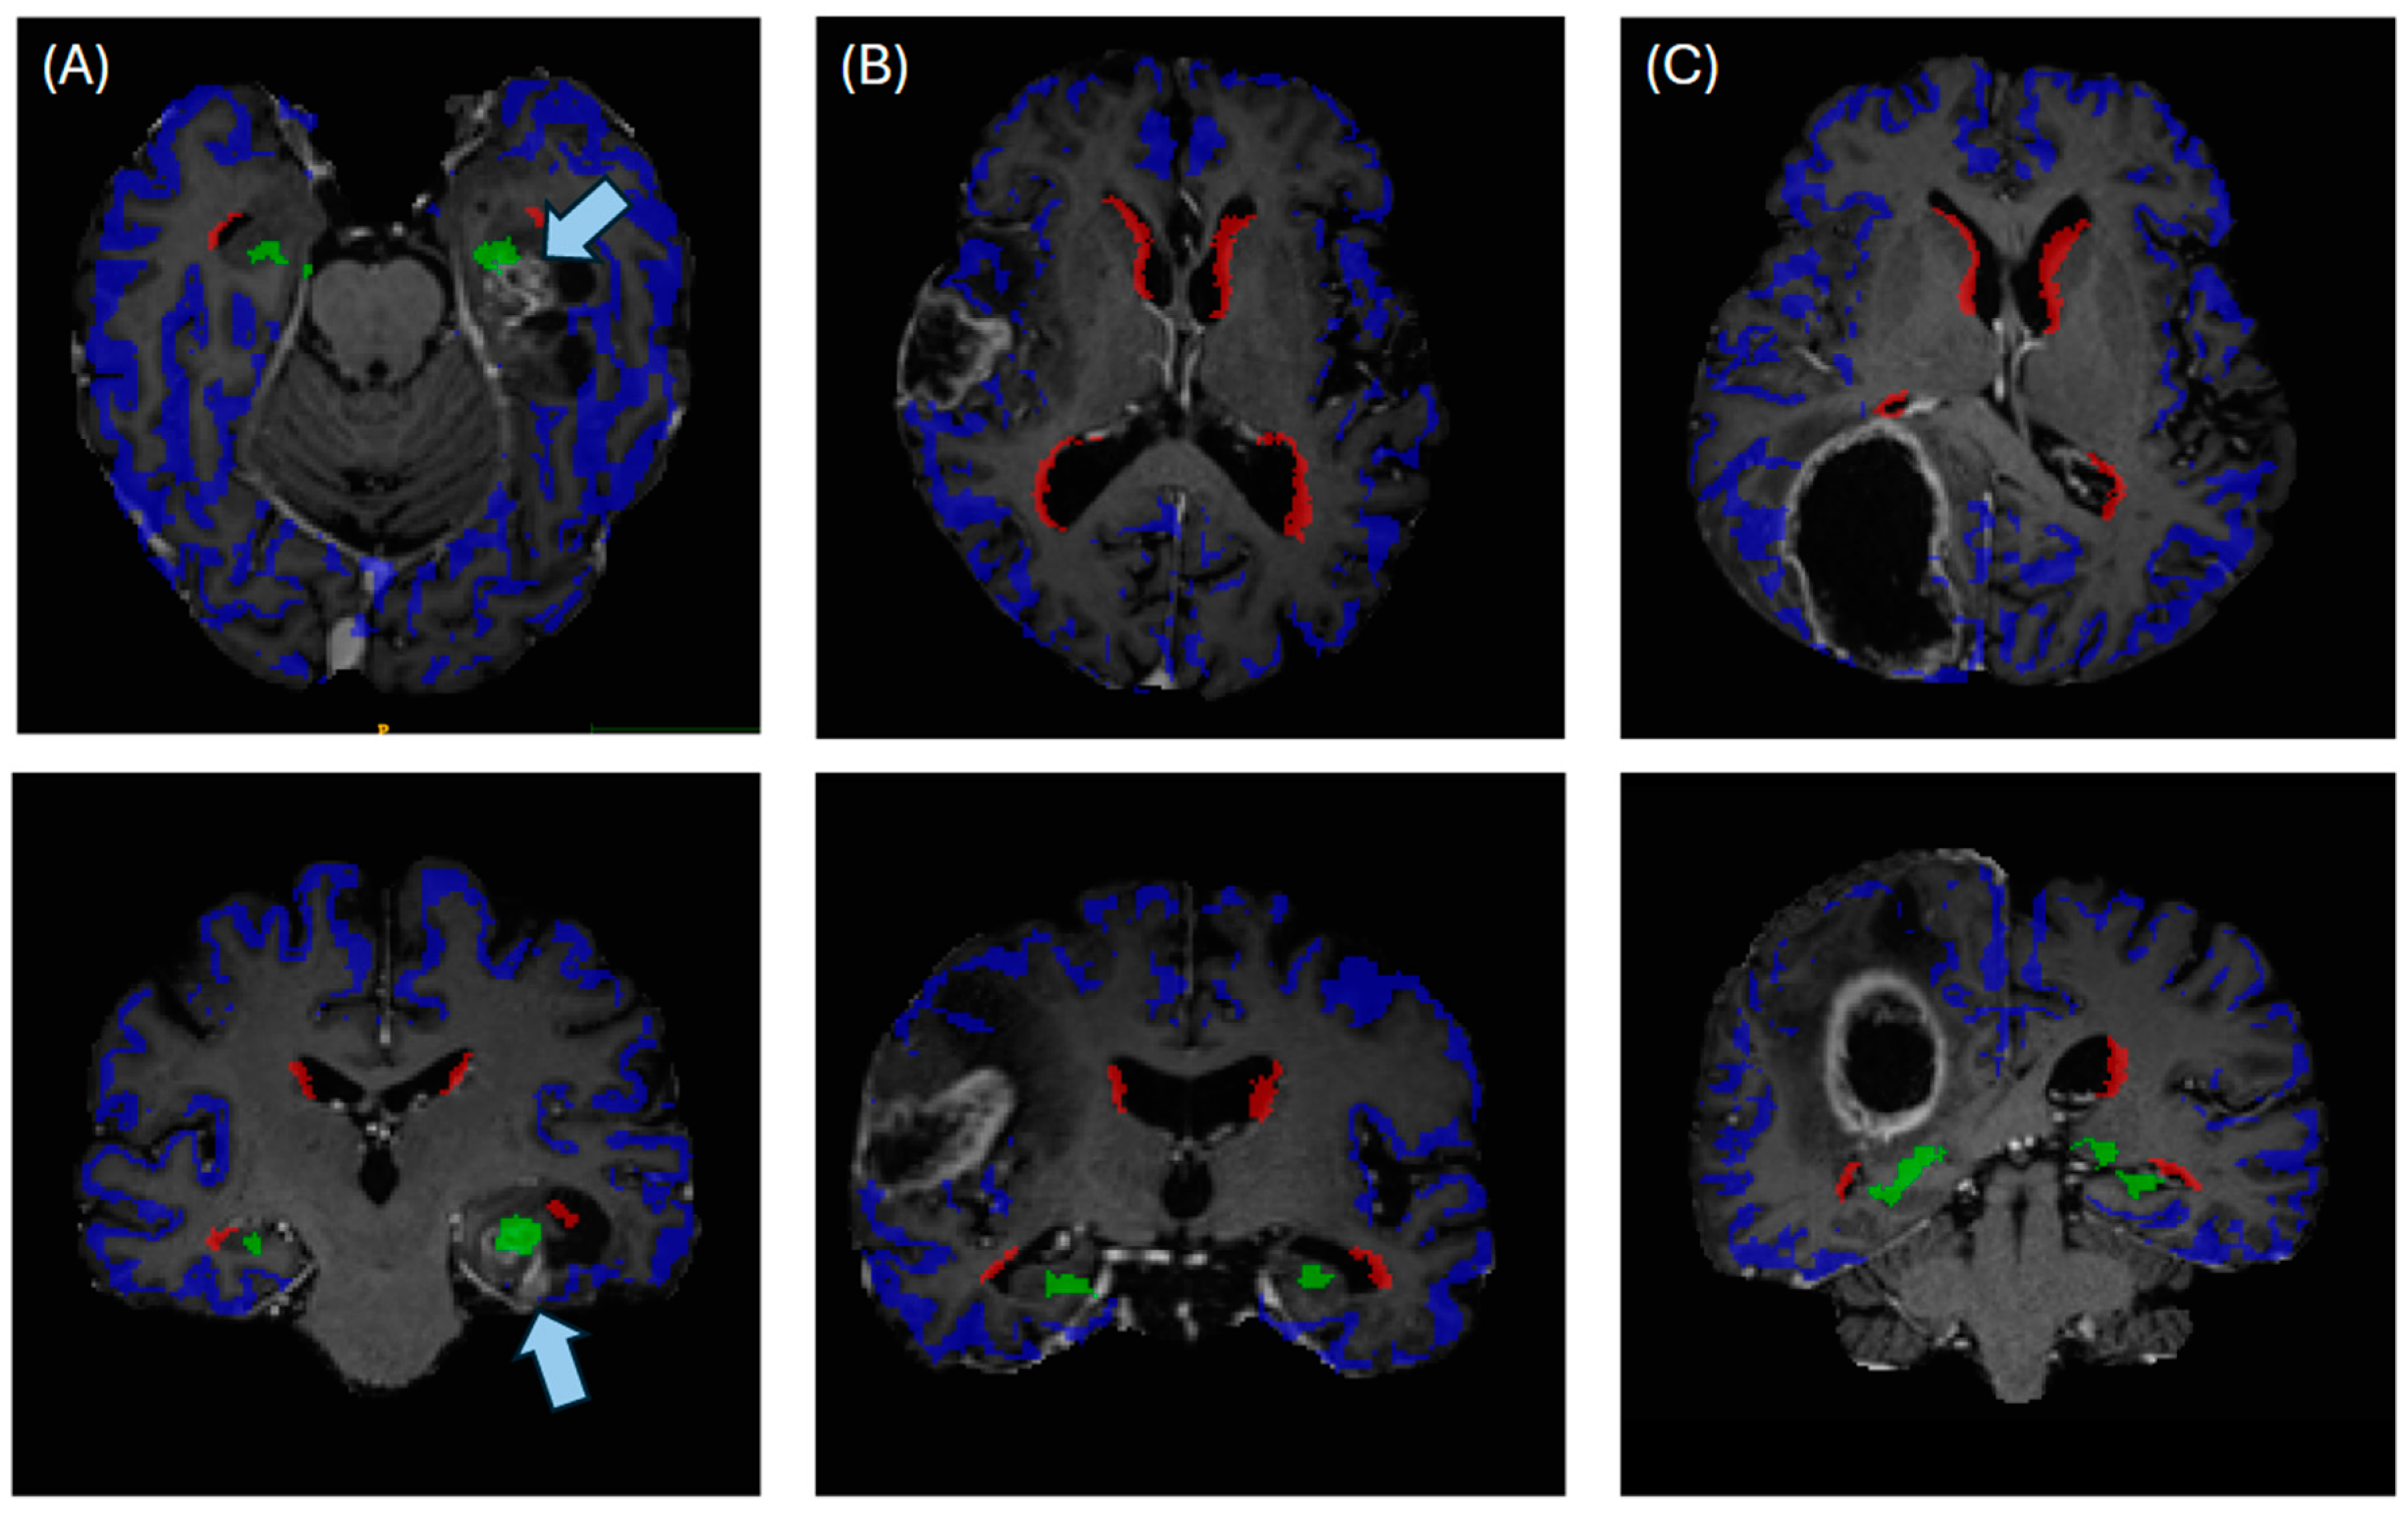

2.3. Automated Segmentation of Neurogenic Zones